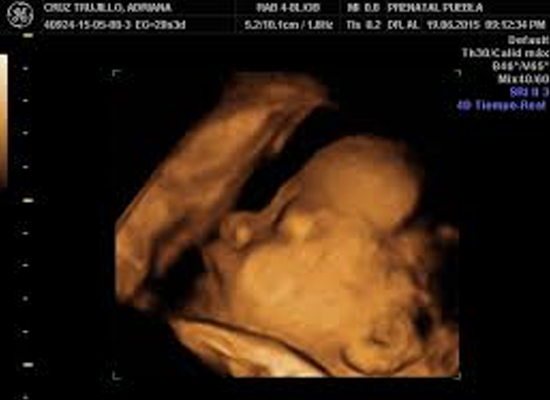

Contamos con equipos de ultrasonido de alto desempeño y resolución de imagen. Con capacidad de realizar estudios de 4 D y elastografia, realizamos todos los estudios de ultrasonido como son:

• Ultrasonido Ginegco-Obstetricia (ultrasonido estructural de embarazo, ultrasonido vagina, ultrasonido de ovarios y útero, etc.)

• Ultrasonido estructural semana 11-14 de embarazo

El estudio de ultrasonido consiste en la obtención de imágenes del cuerpo humano producidas por los ecos reflejados a un dispositivo llamado transductor que a su vez los envía a la computadora del equipo para la reconstrucción de las imágenes correspondientes. Este método de imagen tiene la gran ventaja de la producción de imágenes sin la utilización de ningún tipo de radiación y en tiempo real que además es un método 100% inocuo para el organismo.